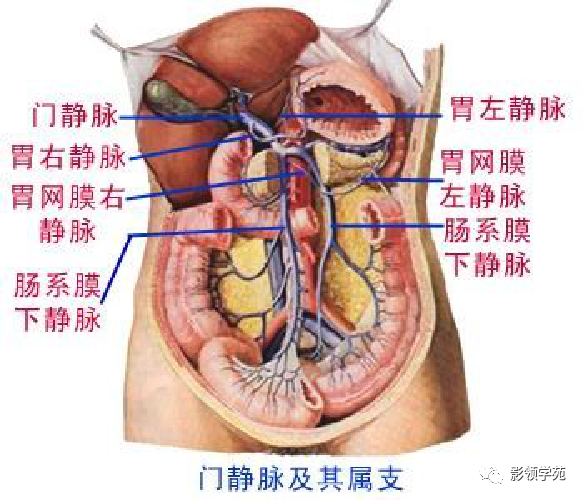

腹部动静脉

腹部动静脉